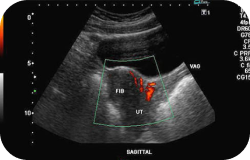

Ultrasound scan of the pelvic region to evaluate the bladder and reproductive organs, helping detect cysts, masses, enlargements, or other abnormalities.

A real-time ultrasound scan is performed to evaluate the organs and structures in the lower abdominal area. This test is used to look at the bladder as well as the ovaries, uterus, cervix, and fallopian tubes to detect cysts, masses, and any other abnormalities.